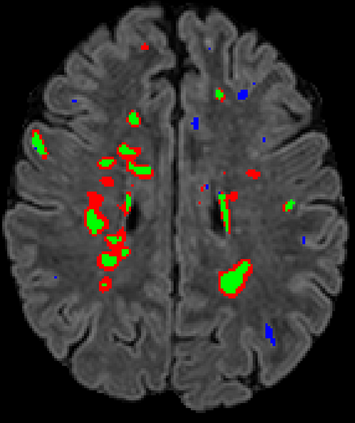

Recently, segmentation methods based on Convolutional Neural Networks (CNNs) showed promising performance in automatic Multiple Sclerosis (MS) lesions segmentation. These techniques have even outperformed human experts in controlled evaluation conditions such as Longitudinal MS Lesion Segmentation Challenge (ISBI Challenge). However state-of-the-art approaches trained to perform well on highly-controlled datasets fail to generalize on clinical data from unseen datasets. Instead of proposing another improvement of the segmentation accuracy, we propose a novel method robust to domain shift and performing well on unseen datasets, called DeepLesionBrain (DLB). This generalization property results from three main contributions. First, DLB is based on a large group of compact 3D CNNs. This spatially distributed strategy ensures a robust prediction despite the risk of generalization failure of some individual networks. Second, DLB includes a new image quality data augmentation to reduce dependency to training data specificity (e.g., acquisition protocol). Finally, to learn a more generalizable representation of MS lesions, we propose a hierarchical specialization learning (HSL). HSL is performed by pre-training a generic network over the whole brain, before using its weights as initialization to locally specialized networks. By this end, DLB learns both generic features extracted at global image level and specific features extracted at local image level. DLB generalization was validated in cross-dataset experiments on MSSEG'16, ISBI challenge, and in-house datasets. During experiments, DLB showed higher segmentation accuracy, better segmentation consistency and greater generalization performance compared to state-of-the-art methods. Therefore, DLB offers a robust framework well-suited for clinical practice.